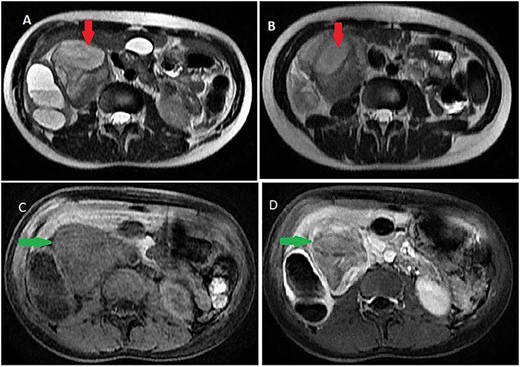

On magnetic resonance imaging (MRI), tumor signal was heterogeneously high in T2-weighted images, while iso to low in T1-weighted images delayed heterogeneous enhancement with some septa and areas of necrosis (Fig. 2).

Abdominal MRI showing a retroperitoneal mass; (A and B) axial T2-weighted images show heterogeneous high signal in the lesion; (C and D) axial T1-weighted image, before (C) and after (D) dynamic sequences with contrast showing a delayed heterogeneous enhancement with some septa and areas of necrosis within the mass.